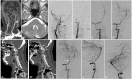

Background: The ideal treatment for patients who survive from acute vertebrobasilar artery occlusion but develop aggressive ischemic events despite maximal medical therapy in the early non-acute stage is unknown. This paper reports the technical feasibility and outcome of staged endovascular treatment in a series of such patients with symptomatic intracranial vertebral artery occlusion. Methods: Ten consecutive patients who presented with aggressive ischemic events in the early non-acute stage of intracranial vertebral artery occlusion from Jan 2015 to Nov 2020 were retrospectively reviewed. Among them, eight male and two female patients with a mean age of 66.7 years developed aggressive ischemic events, and the NIHSS score was elevated by a median of 7 points despite medical therapy. All patients received staged endovascular treatment 4-21 days from onset, at an average of 11 days. The strategy of staged treatment was as follows: first, a microwire was passed through the portion of the occlusion, which was then dilated with balloon inflation to maintain the perfusion above TICI grade 2b. Then, with the use of antiplatelet drugs, the residual intravascular thrombus was gradually eliminated by the continuous perfusion and an activated fibrinolytic system, leaving the residual stenosis. A second stage of angioplasty with stent implantation was subsequently performed if residual stenosis was ≥50%. The NIHSS scores and mRS scores were compared between pre- and post-endovascular treatment groups and in the follow-up period. Results: Technical success was achieved in 9 patients who received staged endovascular treatment (perforation occurred in one patient during the first stage). The NIHSS scores were significantly improved, with a median score 7 points lower on discharge compared with the scores for the most severe status. Favorable outcomes with mRS score ≤ 2 were achieved in 7 and 9 patients at the 3-month follow-up and the latest follow-up, respectively, which was better than the preoperative status. Conclusion: Staged endovascular treatment might be a safe, efficient, and viable option in carefully selected patients with symptomatic intracranial vertebral artery occlusion in the early non-acute stage. However, this needs to be confirmed by further investigation, preferably in a large, controlled setting.